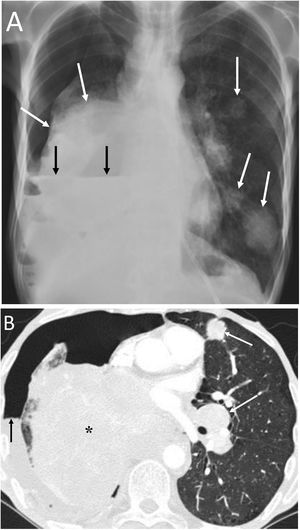

Spontaneous pneumothorax (PTX) is a very rare presentation of malignant pleural mesothelioma (Fig. 10) and is more common in patients over 40 years of age.26 Possible mechanisms are: rupture of necrotic tumour nodules, obstruction of peripheral pulmonary bronchi by tumour nodules with formation of subpleural bullae, and invasion of the pulmonary parenchyma by mesothelioma.27 Pleural drainage is usually ineffective and the lung cannot be re-expanded.27

A 69-year-old man with progressive dyspnoea and chest pain. A) The chest X-ray showed an air-fluid level that occupied the entire right hemithorax, indicative of a hydropneumothorax (white arrows). B) Computed tomography after pleural drainage showed the presence of nodular pleural thickening with involvement of the mediastinal pleura (white asterisks). Videothoracoscopy revealed the presence of multiple right pleural nodules, a biopsy of which was positive for pleural mesothelioma.

Spontaneous PTX has been described in 0.03%−0.05% of patients with primary lung neoplasia (Fig. 11), with a clear predominance of males (90%).28 Presentation of pulmonary neoplasia as spontaneous PTX appears in patients with advanced disease.28 An underlying lung neoplasm should be ruled out in patients under 40 years of age with recurrent pneumothorax, or in patients over 40 years with a history of smoking, chronic bronchitis or emphysema, with incomplete lung expansion or a lung mass on chest radiograph after pleural drainage.28

A 57-year-old man with a disseminated lung neoplasm undergoing chemotherapy. A) The chest X-ray revealed a right lung mass with left lung nodules (white arrows) and an air-fluid level in the right hemithorax due to hydropneumothorax (black arrows). B) The computed tomography scan revealed a large right lung mass (black asterisk), lung nodules and masses and contralateral hilar adenopathies (white arrows), and the right hydropneumothorax (black arrow). The patient died within a few days.